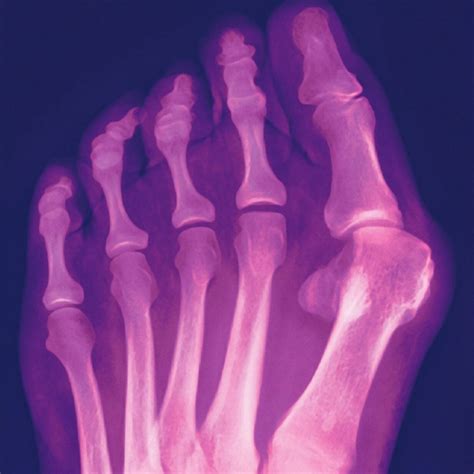

Once the images are captured, a radiologist or your podiatrist will analyze the films. They look specifically at how the first metatarsal bone has deviated away from the second metatarsal. The following table illustrates how medical professionals generally categorize the severity based on the angles derived from the X-ray:

Severity Hallux Valgus Angle (HVA) Clinical Implication

Mild Less than 20 degrees Usually manageable with conservative care

Moderate 20 to 40 degrees May require orthopedic inserts or orthotics

Severe Greater than 40 degrees Often requires surgical intervention to correct

In addition to the standard top-down view, doctors may also order a lateral view or an oblique view. These extra angles help assess if there is a rotation of the big toe, which is a common component of progressive bunions.